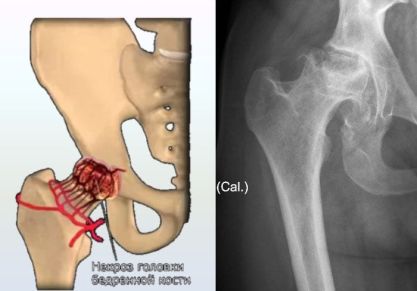

Тазобедренный сустав – это самое большое сочленение в организме человека, который отвечает за способность человека прямо передвигаться. Естественно, что боль в этой части скелета может привести к тому, что нижние конечности двигаться не будут. Тазобедренный сустав испытывает ежедневную колоссальную нагрузку, так как на него давить вся верхняя половина тела. Именное это соединение костей повреждается больше всего, особенно у пожилых людей. Причиной боли в этой части тела бывает вывих, врожденная патология (дисплазия), коксартроз, инфекционное поражение, воспалительный процесс, перелом или отмирание головки бедренной кости. Спровоцировать болевой синдром может и аутоиммунное заболевание. Осложнения заболеваний представленного сочленения очень серьезные, поэтому следует обязательно обратиться к доктору при первых признаках его поражения.